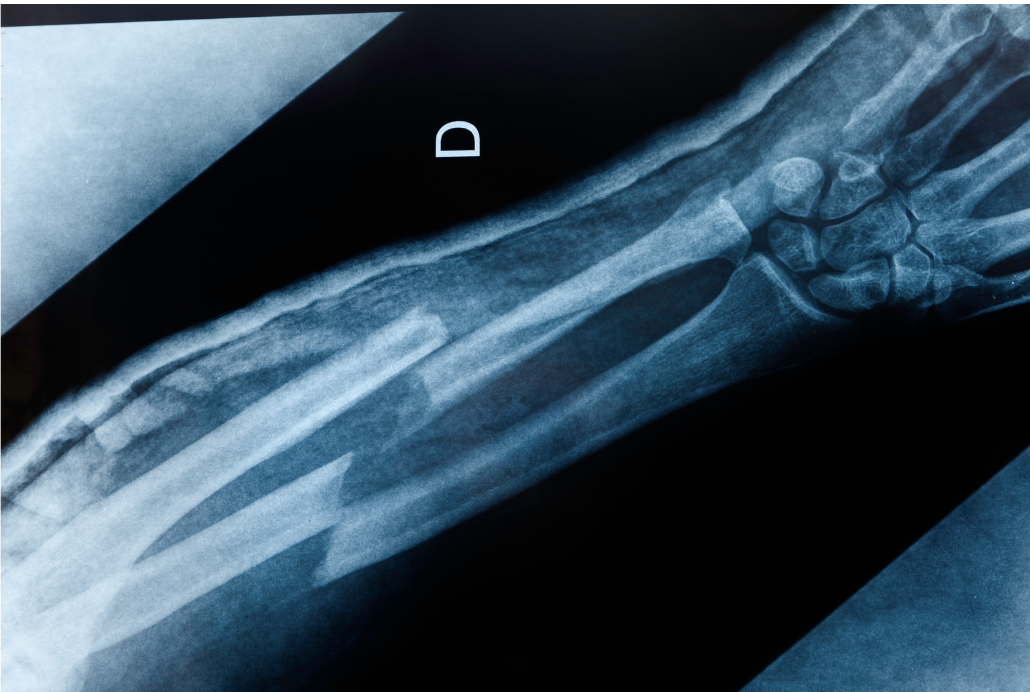

That’s the issue the researchers at the University of Oregon tackled. They created a series of small implants with sensors that can provide data in real time at the injury site to help better determine if a bone needs more resistance rehab or if it has been overworked. In a technological study, the implants “significantly improved” the healing time for broken femurs in lab rats, cutting down a healing time from four-to-six months down to as little as eight weeks.

While monitoring their bones using the sensors, the researchers found that the rodents that were given proper physical therapy in their exercise wheels with increasing resistance to promote building strength had their femurs heal much faster and more effectively than rodents that were sedentary. This included rodents that needed their training lowered at times depending on the data retrieved from the sensors.